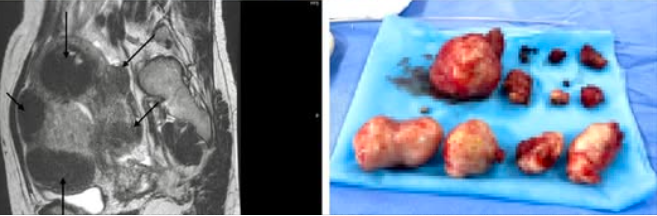

Kết quả siêu âm phát hiện bệnh nhân có nhiều khối u xơ nằm rải rác bao quanh tử cung, khối lớn nhất nằm ở thành trái L4 gần vòi tử cung, kích thước 79x68mm và L6 kích thước 68x39mm, khối u xơ ở đáy L5 có kích thước 51X48mm, có vôi hóa viền.

U xơ tử cung trên phim chụp và được lấy ra của bệnh nhân đa u xơ tử cung - Ảnh BVCC

Sau khi hội chẩn chuyên khoa, các bác sĩ chẩn đoán bệnh nhân bị đa u xơ tử cung phức tạp, chỉ định phẫu thuật gây mê nội khí quản để bóc tách u xơ. Quá trình bóc tách khối u, sau khi xử trí gỡ dính phức tạp mặt sau tử cung vào cùng đồ, mạc nối và buồng trứng trái, các bác sĩ đã tiến hành bóc thành công 11 khối u xơ, bảo tồn tử cung cho bệnh nhân, các mẫu bệnh phẩm được gửi giải phẫu bệnh, xét nghiệm, rất may các u đều lành tính.